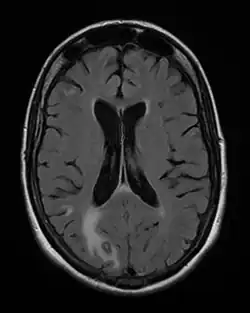

Toxoplasmose cérébrale

Toxoplasmose cérébrale avec implication principale dans le lobe occipital droit (en bas et à gauche de l'image). Femme de 48 ans atteinte du SIDA.

On décrit de rares cas où un sujet VIH+, sans immunité anti-toxoplasmique (pas de contact antérieur) contracte une toxoplasmose, mais le plus souvent il s'agit de patients immunisés contre la toxoplasmose, donc porteurs de kystes qui réactivent l'infection lors d'une baisse conséquente de leurs défenses immunitaires ; généralement, ils présentent une toxoplasmose cérébrale.

La toxoplasmose cérébrale est une maladie opportuniste dont la survenue chez les personnes séropositives marque l'évolution de l'infection par le VIH au stade de sida. Elle survient en règle générale chez des sujets séropositifs au VIH, ayant moins de 200 lymphocytes T CD4+, avec une sérologie toxoplasmique positive et ne recevant pas de prophylaxie spécifique. C'est alors que les bradyzoïtes libèrent les tachyzoïtes qui essaiment dans tout le corps via le système sanguin[37]. En 2008 en France, la toxoplasmose cérébrale représentait 12 % des personnes qui découvraient leur séropositivité au VIH après le déclenchement d'une affection opportuniste[38].